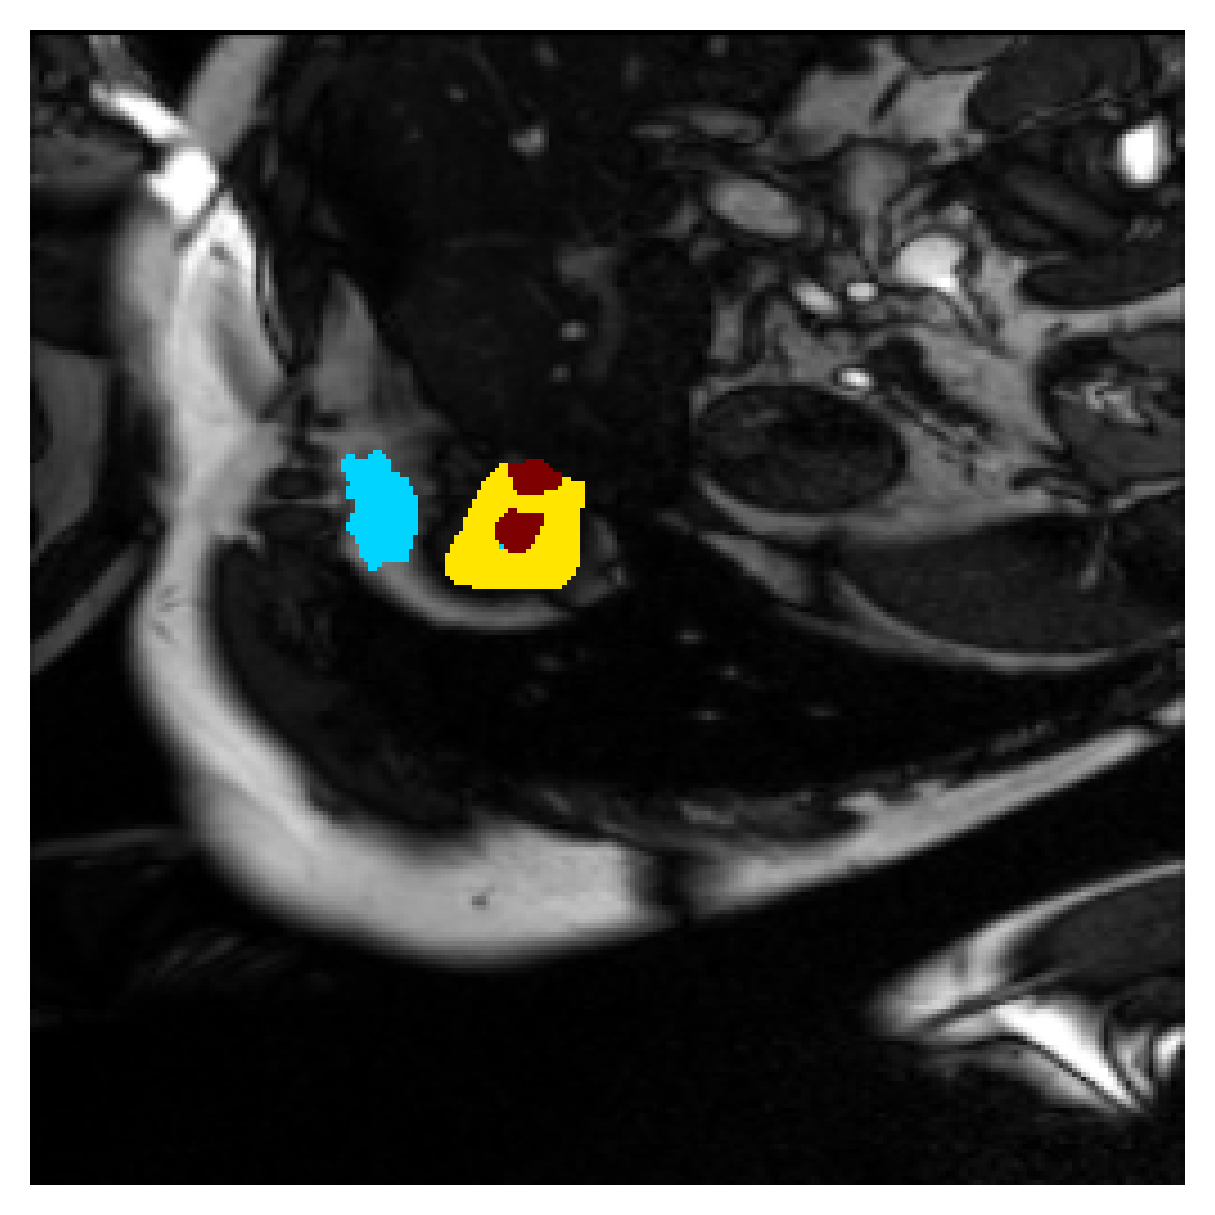

We normalize the volumes and resize the slices to pixels. As the official dataset comes with full annotations, we create a synthetic point ground truth. This is done by first randomly choosing the centers of the point annotations within the class masks, followed by filling an ellipse with axes lengths of and (in pixels) around each center. The intersections of these elliptic discs with the underlying full annotations are then used as our point ground truth. See Figure 2 for an example of the created weak annotation mask. The point annotations are created for every slice, one for each foreground object present in the slice.

Qualitative comparison

| (a) Ground truth | (b) , full | (c) , weak | (d) |

| (full) | supervision | supervision | |

| (e) | (f) | (g) | (h) CRF-loss |

In Figure 6 we provide qualitative results on a number of randomly chosen test set slices. Upon visual inspection, we can observe that training with the intensity-aware distances (particularly with and ) follows the image gradients better and is better at recovering the underlying shape than the Euclidean version. The CRF-loss seems to recover the shape of the myocardium and left ventricle to some extent, but fails entirely on the right ventricle.